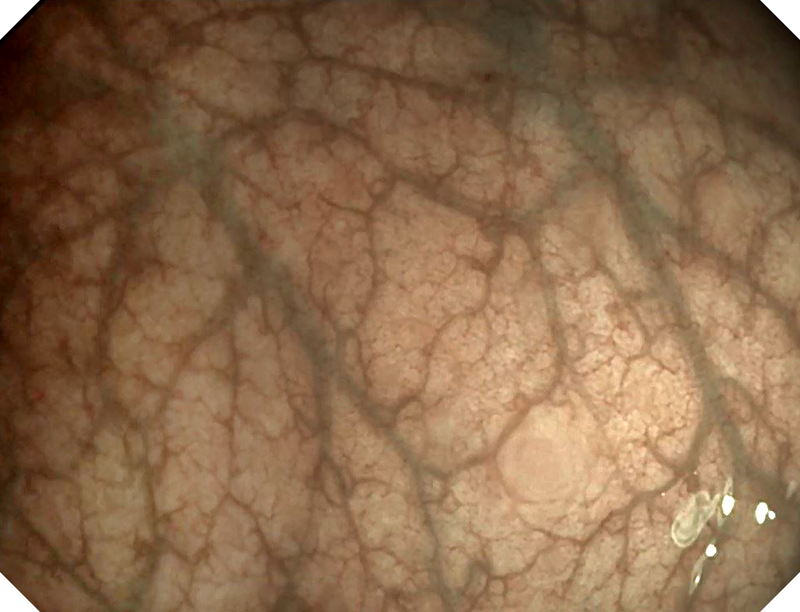

百万级像素传感器,1080P视频信号输出,图像清晰

具有聚谱成像技术(SFI)及光电复合染色成像技术(VIST) 能够呈现粘膜细节及病变特征

白光图像

白光图像

SFI图像

SFI图像

VIST图像

VIST图像